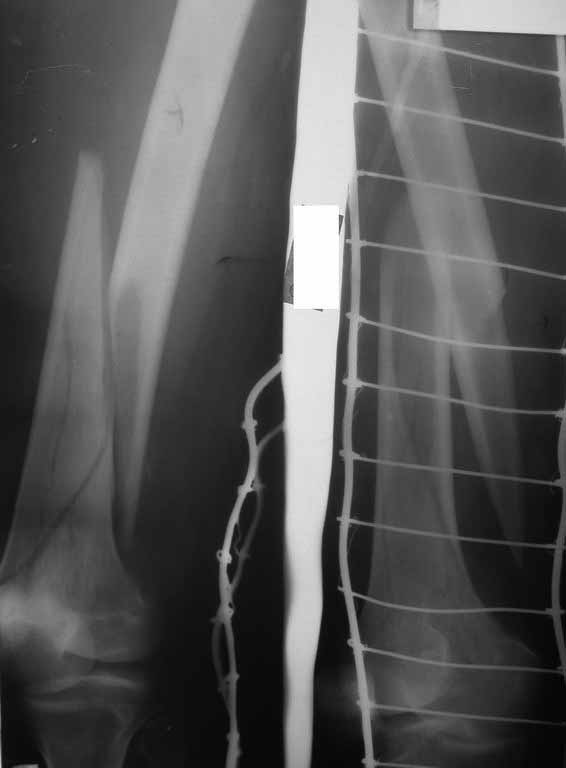

Представляю вам один из наших недавних случаев выполнения малоинвазивного остеосинтеза бедренной кости обычной пластиной 95 градусов. Длина восстановлена с помощью дистрактора (по сути это основная и б(о)льшая часть репозиции). Произведено два небольших доступа, проведена спица направитель. Рентген-контроль для подтверждения достаточной длины/оси (ЭОП использовался в другой операционной). Создание туннеля обратной стороной фиксатора. Поворот фиксатора, введение клинка по спице. Фиксация проксимального и дистального концов пластины.

[ Ответить ]